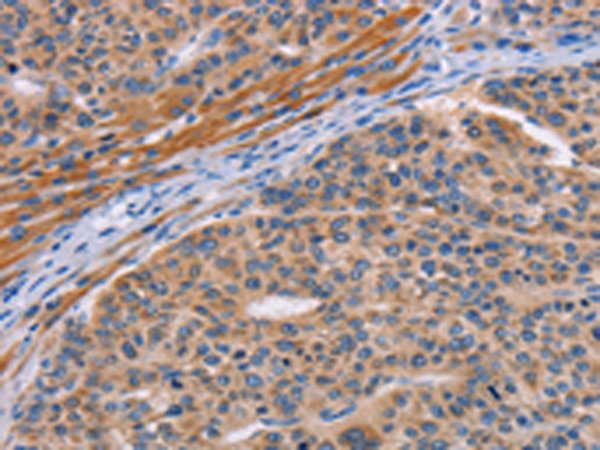

分类: 科研抗体货号: P07818别名: CDG1L; DIBD1; LOH11CR1J应用: IHC反应种属: Human, Mouse